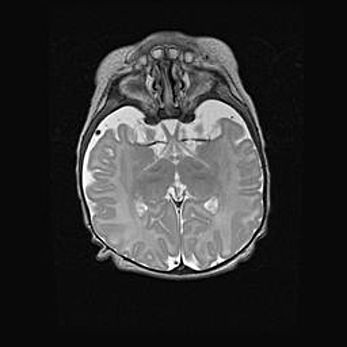

Мальформация Денди-Уокера. Киста задней черепной ямки.

Агенезия мозолистого тела.

Возраст: 2,5 месяца

Вес: 2420 г

Пол: женский

Окружность головы: 37 см

Срок гестации: 32 недели

Мальформация Денди—Уокера — редкий вид патологии ЦНС, представляющий собой врожденный порок развития каудального отдела ствола и червя мозжечка, ведущий к неполному раскрытию срединной (Мажанди) и латеральных (Лушка) апертур IV желудочка мозга. Для этогно синдрома характерна триада симптомов: гипотрофия червя мозжечка и/или полушарий мозжечка, кисты задней черепной ямки, гидроцефалия различной степени. В 70% случаев порок сочетается и с другими аномалиями головного мозга, в частности с агенезией мозолистого тела.